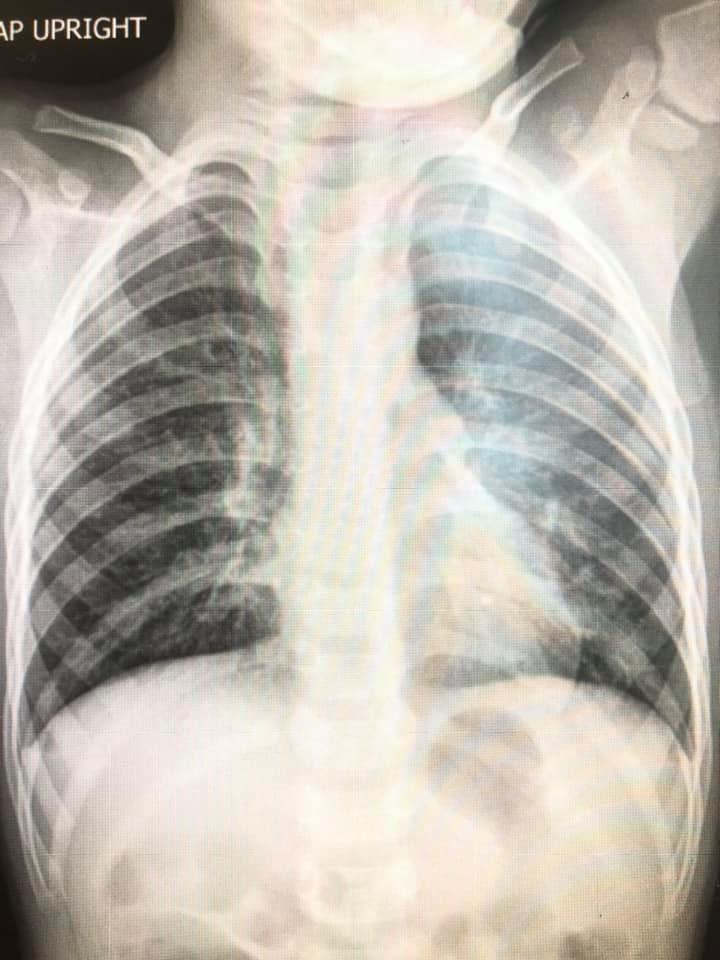

เผยภาพปอดเด็กป่วย RSV ชี้ ไม่มีวัคซีน ไม่มียา ต้องรักษาตามอาการ แนะวิธีป้องกัน งดจูบ หอม สวมหน้ากากอนามัย งดไปแหล่งคนเยอะ ทำความสะอาดของเล่น

1. มาด้วยอาการ ไข้ ไอ เสมหะ หอบเหนื่อย มีอาการน้อยถึงรุนแรง

2. มักพบในเด็กอายุน้อยกว่า 5 ปี ยิ่งอายุน้อยยิ่งรุนแรง กลุ่มเสี่ยง คือ อายุน้อย มีโรคประจำตัวปอดหรือหัวใจ คลอดก่อนกำหนด

7. การพยากรณ์โรค : ปอดบวม ปอดอักเสบ ใช้เวลารักษา 3-7 วันกรณีไม่รุนแรง ถ้ารุนแรงอาจใช้เวลา 10-21 วัน

ภาพจาก เฟซบุ๊ก Infectious ง่ายนิดเดียว